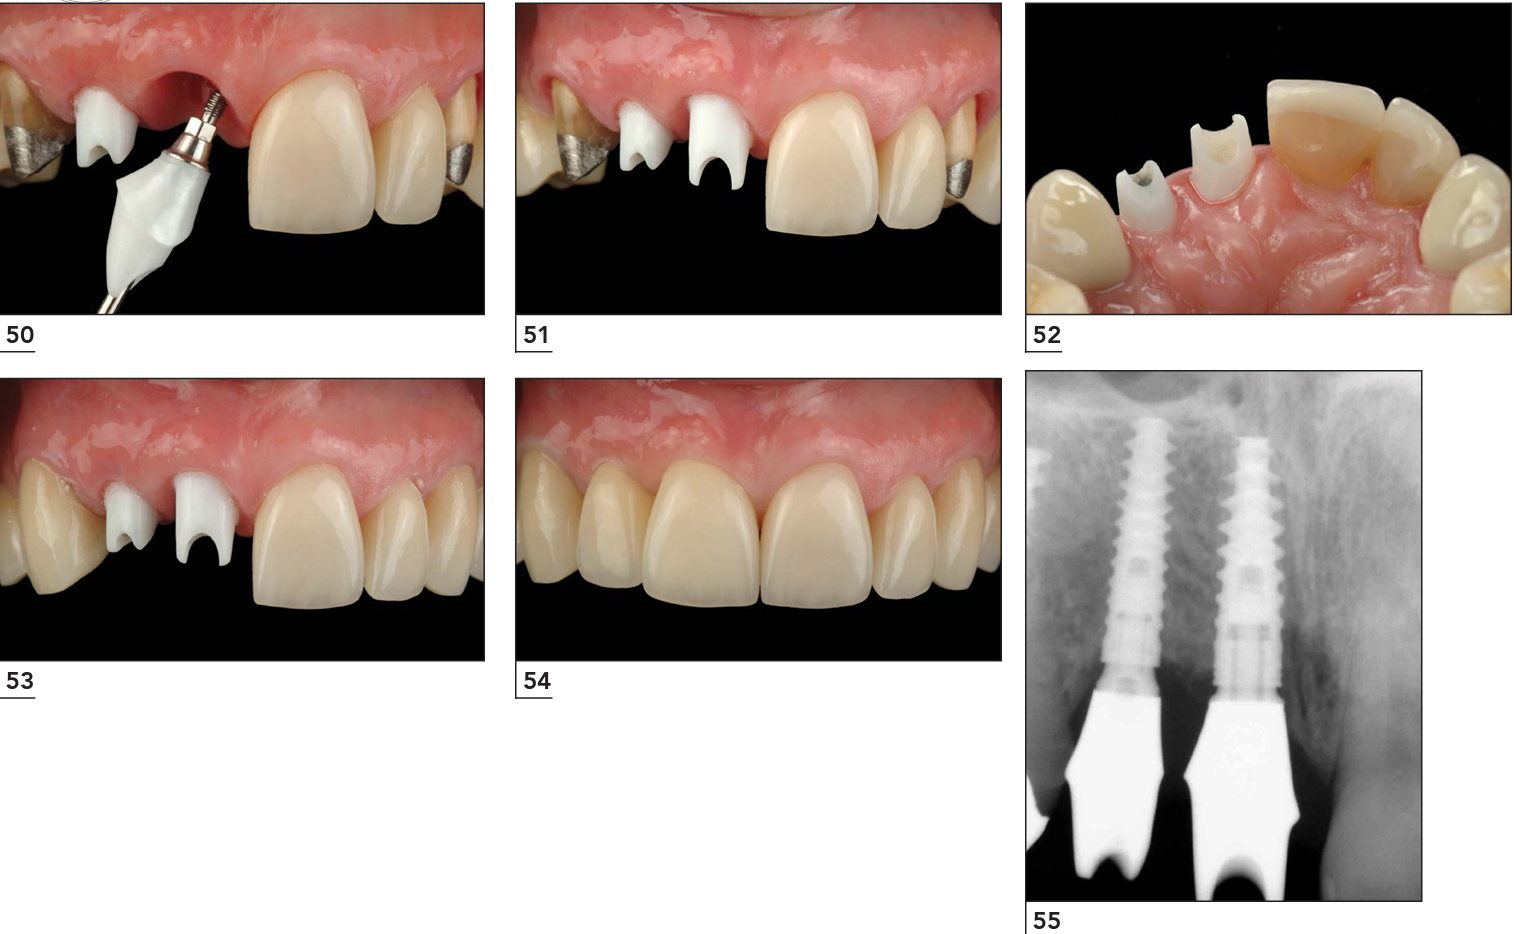

Trụ phục hình cá nhân hóa bằng Zirconia

Hình ảnh gắn trụ phục hình và gắn răng sứ. Một trường hợp trồng implant răng cửa bằng giải pháp DCT tại Lạc Việt Intech.

Một trường hợp sử dụng trụ phục hình các nhân hóa bằng zirconia.

So sánh với một trường hợp sử dụng trụ phục hình sản xuất sẵn (đã được mài mặt ngoài để xóa hình thể tròn).